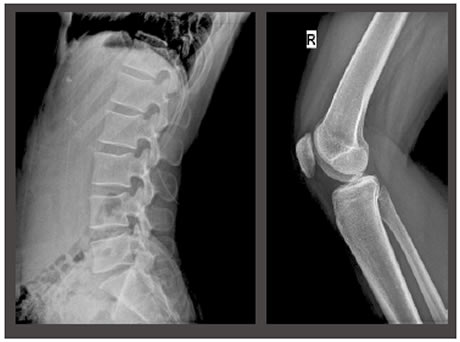

With the configuration of High frequency generator, High-end Tube, Advanced Flat Panel Detector and Functional software support, the system bring high image quality with minimum exposure dose.

The extraordinary flexibility of DigiEye 760 makes the system ideal for patients position, including physically restricted ones. Besides the routine positions, by the application of portable Flat Panel Detector, all the special advanced positions can be easily projected.